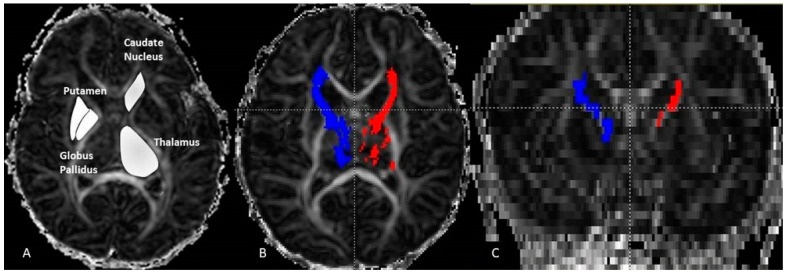

The thalamo-cortical fiber (THC) tracking was carried out with DTI Studio software (Department of Radiology, Johns Hopkins University, Baltimore, MD, USA) using the deterministic FACT algorithm (fiber assignment continuous tracking) and the following two rejection criteria: fractional anisotropy (FA) < 0.15 or angulation > 70°. The seed regions were manually drawn on each axial slice of the TH on FA maps (4 to 5 slices). It has been applied with the inclusive “OR” operator. The target regions were selected FA maps at the coronal plane at the level of the genu. This was performed with an exclusive operator “AND”. It was reproduced bilaterally to determine left and right THC pathways. The axial diffusion (AD), the radial diffusion (RD), the apparent diffusion coefficient (ADC) and the FA were measured and averaged separately over the entire left and the entire right THC. For each group (girls, boys and combined) we measured the DTI variables bilaterally on the selected four structures: TH, PT, GB, and CN (Figure 1).

For structure analysis, the delineation of each region was performed manually on each hemisphere. The regions of interest were carefully drawn covering the entire surface area on FA maps because the structure edges are well displayed and easily identified. An experienced scientist with over 10 years of practice carried out the ROI drawings. This procedure was repeated twice (one month apart) to minimize the subjectivity error. The results of the two measures were averaged to perform the statistical comparisons. The delineation was reproduced on axial planes and going through the entire structure. We calculated the DTI variables (AD, RD, ADC and FA) by averaging the measured values. For each of the 4 DTI variables, we calculated the asymmetry index (AI) to identify the dominance hemisphere per structure and gender. Dominance was attributed to the left side if AI value is positive and to the right if it is negative.